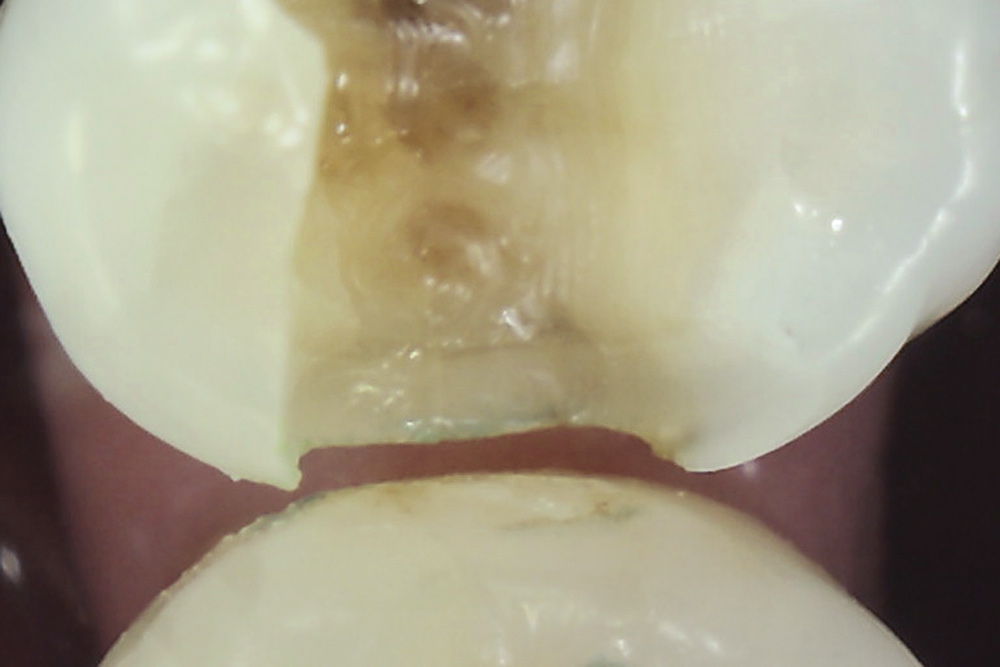

Fig 6. Methylene blue dye staining revealing asymptomatic enamel marginal ridge crack of a maxillary left first molar (mesio-occlusal view).

Figure 6

Fig 7. Existing restoration removal and crack fissurotomy revealing enamel crack (arrow) and caries in tooth shown in Fig 6.

Figure 7

Once a significant asymptomatic enamel crack is diagnosed, to determine its extent the crack is exposed and traced using a minimally invasive exploratory fissurotomy as well as caries removal and/or existing restoration removal whenever indicated (Figure 6 and Figure 7).2,3,17 If the crack is limited to enamel and does not extend into dentin, it can be completely eliminated and treated similarly to caries whereby the condition of the remaining tooth structure dictates the type of the restoration placed and the materials used (Figure 8). For example, moderate-sized cavity preparations can support bonded direct intracoronal resin-based composite restorations (Figure 9).25 This is generally interpreted as cavity preparations in which the isthmus width is less than 50% of the intercuspal distance and the remaining enamel is sound and well supported by dentin. Occlusal adjustment, including removal of excursive interferences, might also be necessary to eliminate localized heavy occlusal forces that are predisposing the tooth to cracking.10,19,26 Occlusal guards also can be fabricated to protect teeth from the damage caused by ongoing bruxism.19